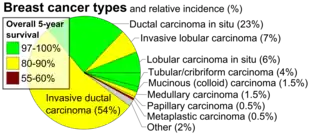

Invasive lobular carcinoma (ILC) is breast cancer arising from the lobules of the mammary glands.[1] It accounts for 5–10% of invasive breast cancer.[2][3] Rare cases of this carcinoma have been diagnosed in men (see male breast cancer).[4]

Overall, the five-year survival rate of invasive lobular carcinoma was approximately 85% in 2003.[9]